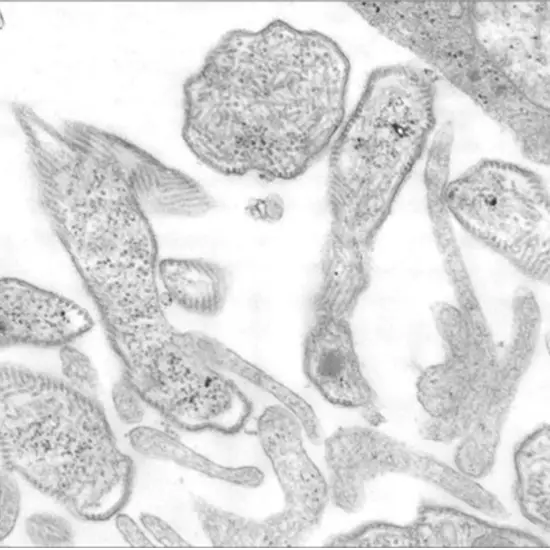

What is the mumps' pathology?

Clinical traits

Myalgia, anorexia, malaise, headache, and low-grade fever are some of the non-specific prodromal symptoms. Parotitis, or the enlargement of a salivary gland, is the usual mumps symptom and lasts for around five days.